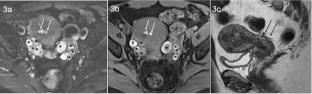

Endometriosis is a common cause of subfertility and infertility through myriad mechanisms. Imaging of endometriosis is critical for its diagnosis, characterization, and treatment. Understanding its imaging appearance, surgical management, and implications for assisted reproductive therapy is essential to providing the most clinically relevant and impactful reports in endometriosis patients. This manuscript will review imaging techniques used to diagnose and characterize endometriosis-related infertility. We will describe relevant imaging findings by anatomic site and review the impact of surgery and ART on its appearance.

Graphical abstract

Abstract Image